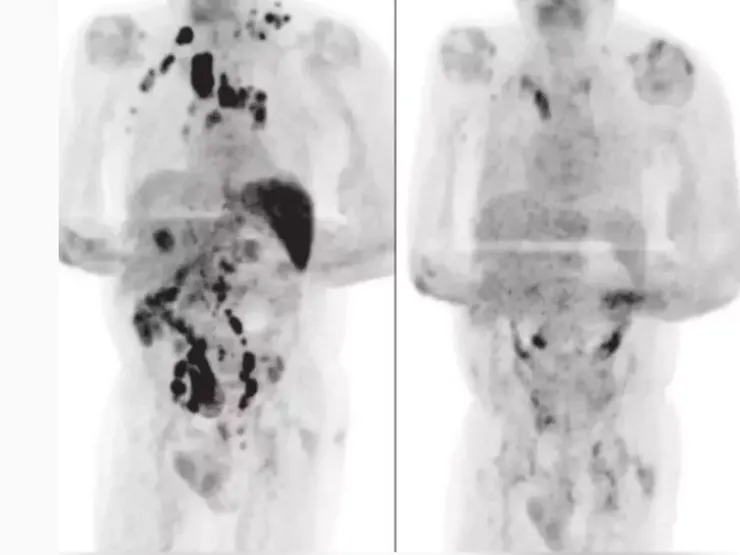

這起因為罹患新冠肺炎,意外使得體內淋巴癌清除盡淨的例子,已經被世界各大媒體廣泛報導。綜合媒體報導,這名罹患嚴重腎病與淋巴癌的61歲男子,日前因為呼吸困難入院,確診新冠肺炎。男子在住院11天後,新冠肺炎情況改善;由於他罹患新冠肺炎,所有的癌症治療全部暫停。等他出院休養4個月後,準備再到醫院進行化療時,腫瘤科醫師為他做斷層掃描,赫然發現,這名病患體內的淋巴腫瘤竟然離奇消失,被掃除得差不多了。